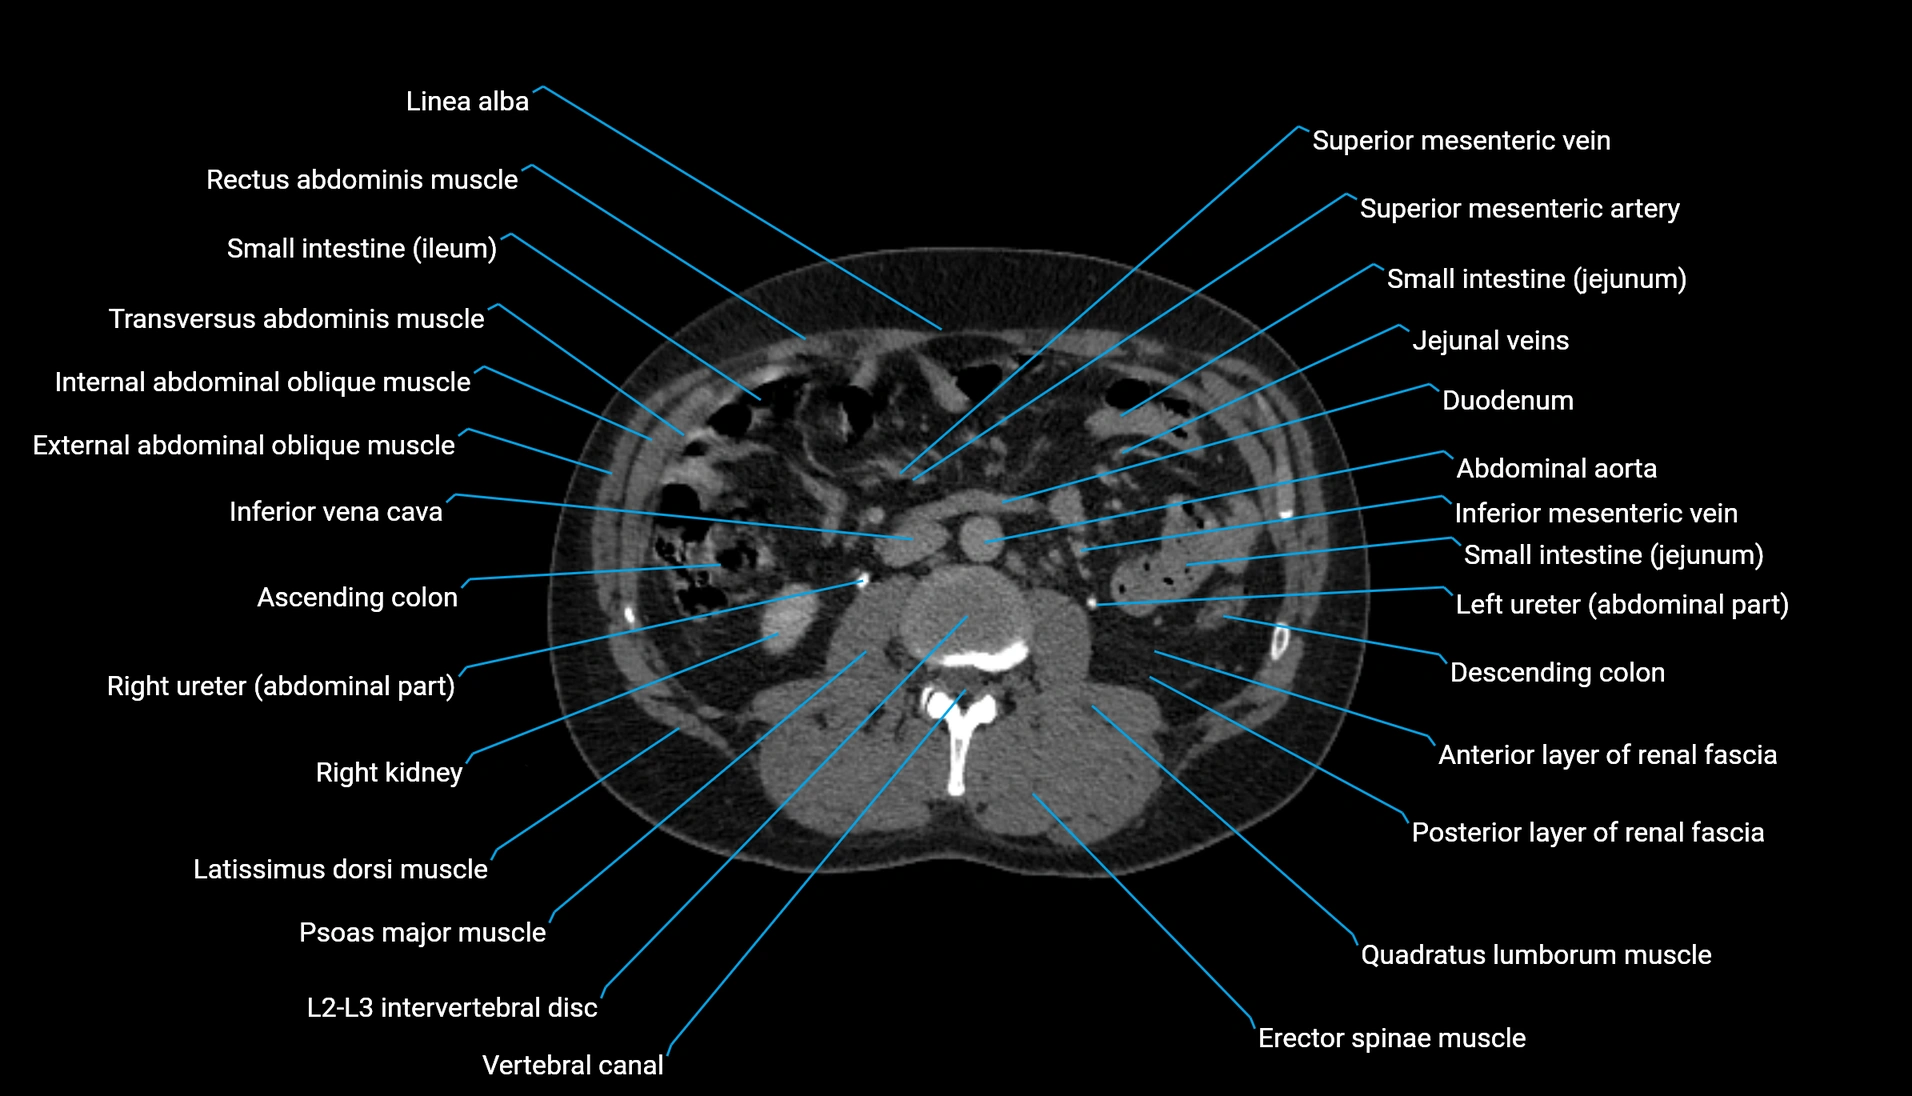

CT Appearance

Non-contrast CT:

-

Demonstrates cortical bone of acetabular rim in excellent detail

Detects fractures, dysplasia, retroversion, or bony overcoverage (pincer impingement)

3D reconstructions used in preoperative hip surgery planning

CT VRT 3D image

CT image